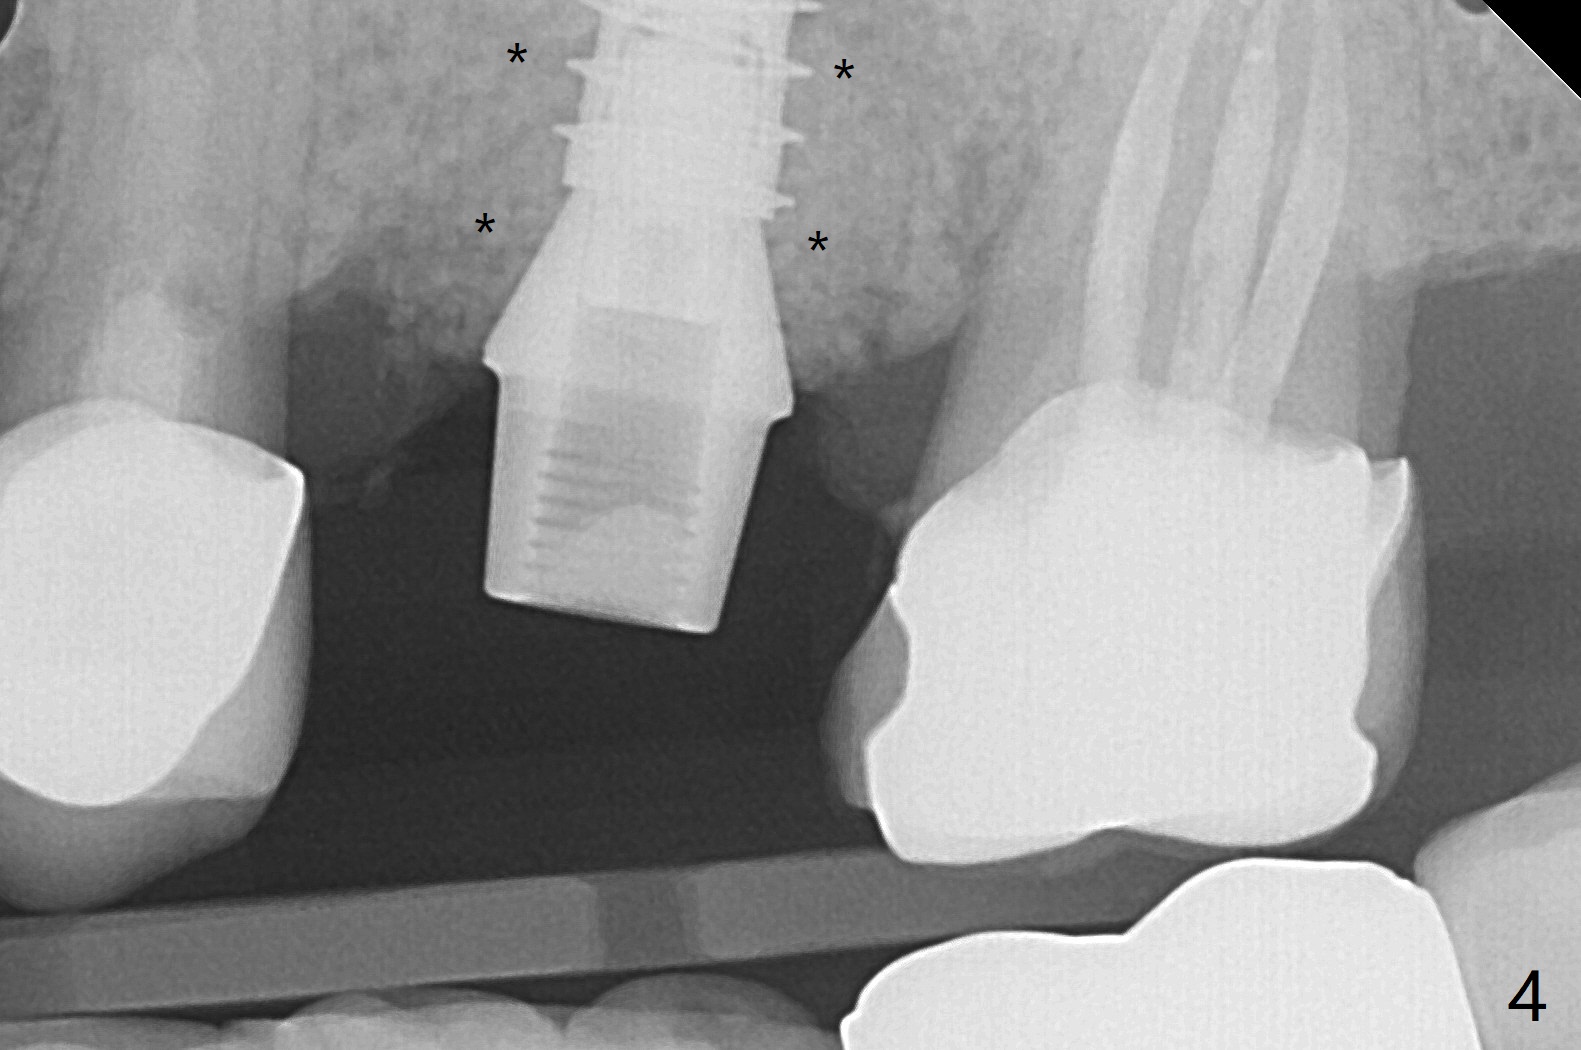

左上6腭侧退缩牙龈(图一:箭头)深部没有骨壁(图二:*),4.5x11毫米植体周围缺损(图三:*)由粘性骨粉(皮质骨,图四:*)填入,即刻临时牙冠(图五:P)覆盖腭侧缺损(空箭头)和PRF膜。临时牙冠颊腭侧做的很宽(图六),目的是关闭腭侧缺损,术后四周在不影响骨粉覆盖情况下,牙冠腭侧适当向颊侧缩小(图七:箭头),但是不应该缩短龈下边缘。术后四个月骨粉形态接近原位骨(图八),但是腭侧软硬组织仍有缺损,炎症。